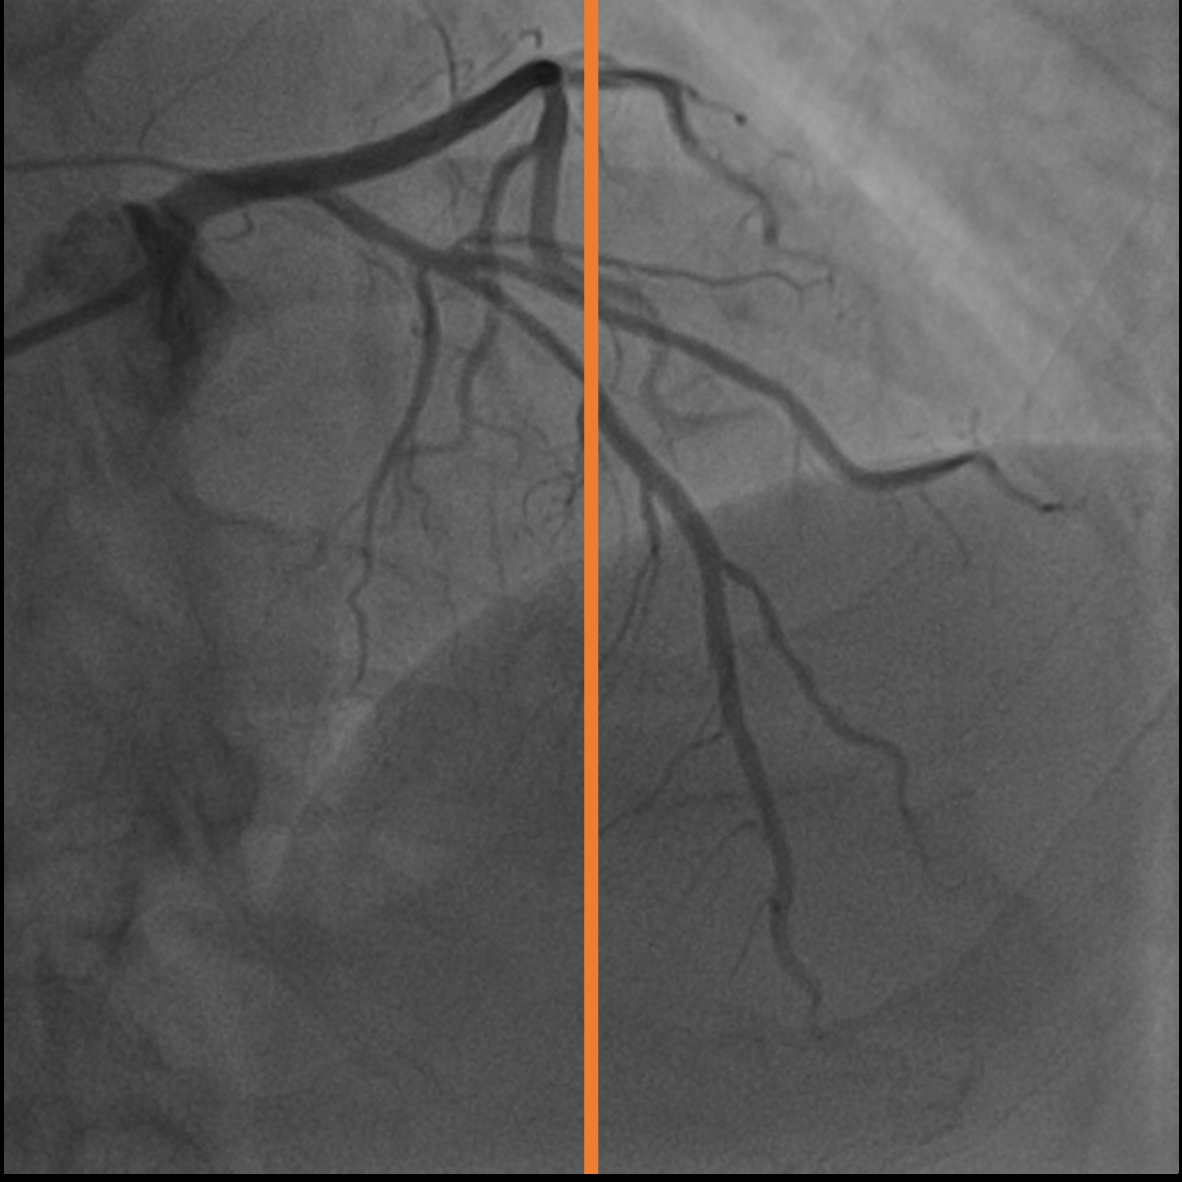

4.1 XACV Dataset

We collect 111 complete records of coronary artery X-ray videos, encompassing the injection, flow through the blood vessels around the heart, and dissipation of the contrast agent. Subsequently, we establish the XACV (X-ray Angiography Coronary Video) dataset. Each video consists of varying numbers of high-resolution coronary artery X-ray images. We invite experienced radiologists to annotate the vascular regions, focusing on one or two frames where the contrast agent is most prominent in each video. The XCAD dataset contains only a single image, and the CADICA video dataset does not provide corresponding ground truth. Therefore, in the following experiments, we conduct all the analyses on our collected XACV dataset and the corresponding GT for each sequence. In Figure 5, we show that compared to other publicly available datasets, XCAD [33] and CADICA [19], our dataset exhibits finer annotations in the vascular regions, providing an advantage for future related tasks. The development and use of our dataset have been approved by our institution’s IRB.